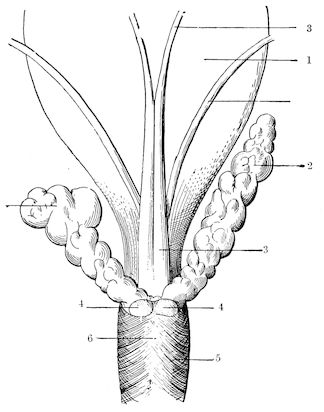

| Castration of the cow | 761 | |||

| Castration of the sow | 765 | |||